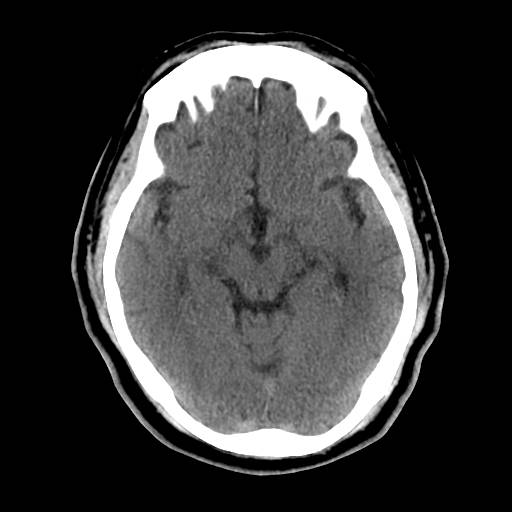

CT(Computed Tomography)とは、日本語でコンピューター断層撮影といいます。エックス線を人体に照射して行い、体内を透過したエックス線量をコンピューターでデータ処理することにより、人体を多方向から輪切り表示にした画像が得られます。

そのため一般のレントゲンではわからないような微細な体内の情報を得ることができます。 患者さんはベッドに寝ていただいて、 その周りをエックス線管球がグルグルとまわる仕組みになっています。 当院では、16列マルチスライスCTを導入しています。

検査の内容によっては、色々な角度からの断面図や3D画像を作ることもできます。撮影部位を変えることで様々な画像を得ることができます。